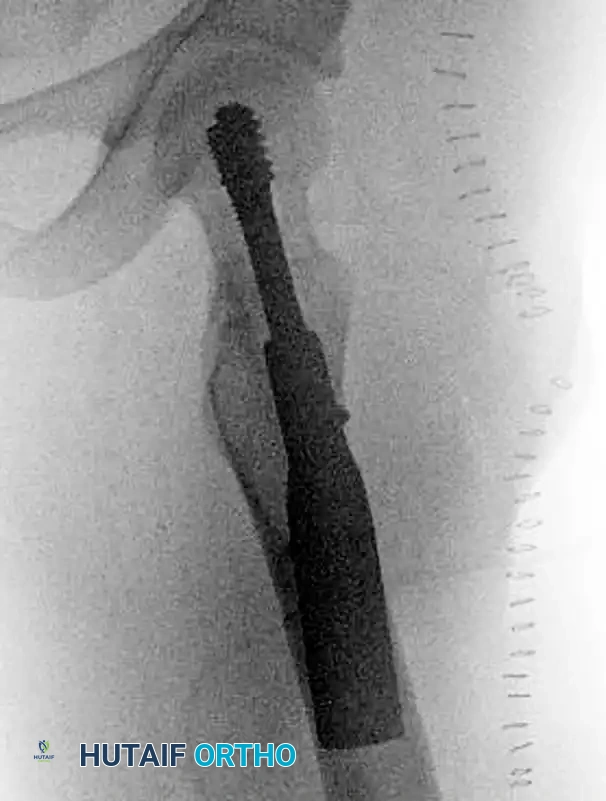

Figure 55-16C: Postoperative lateral radiograph confirming central placement of the lag screw within the femoral head, optimizing the tip-apex distance (TAD).

- Fixed-Angle Devices: For vertically oriented fracture patterns (Pauwels Type III) or basicervical variants, a Sliding Hip Screw (SHS) or Dynamic Hip Screw (DHS) with a derotation screw provides superior biomechanical stability against shear forces compared to multiple cancellous screws.